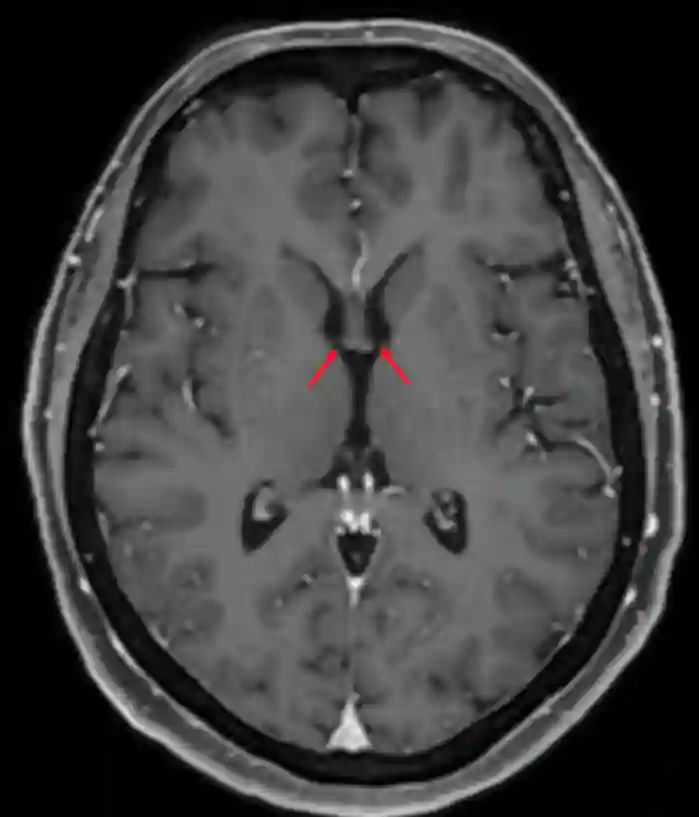

Foramen Monroi im axialen MRI

Axiales MRI Bild (T1 Sequenz mit Kontrastmittel) des Foramen Monrois.